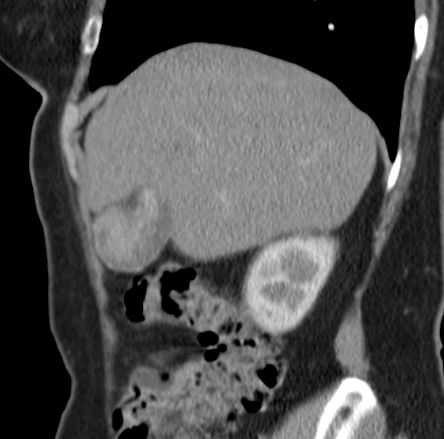

59-jährige Frau mit inzidentellem Gallenblasenkarzinom vor 3 Jahren T2 No

Mo. Jetzt Bauchdeckenmetastase an der Laparoskopienarbe.